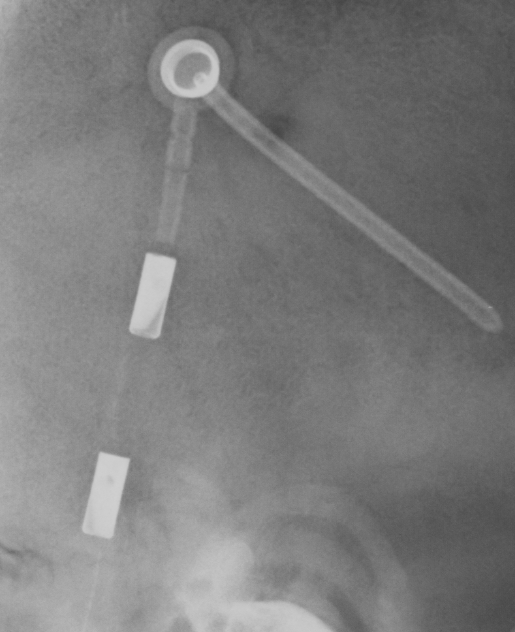

Medtronic Strata NSC

Medtronic Strata NSC valves are adjustable csf shunt valves.